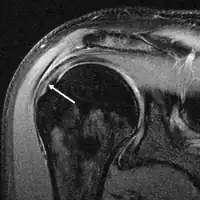

MRI

Magnetic resonance imaging (MRI) and ultrasound[46] are comparable in efficacy and helpful in diagnosis, although both have a false positive rate of 15–20%.[47] MRI can reliably detect most full-thickness tears, although very small pinpoint tears may be missed. In such situations, an MRI combined with an injection of contrast material, an MR-arthrogram, may help to confirm the diagnosis. It should be realized that a normal MRI cannot fully rule out a small tear (a false negative) while partial-thickness tears are not as reliably detected.[48] While MRI is sensitive in identifying tendon degeneration (tendinopathy), it may not reliably distinguish between a degenerative tendon and a partially torn tendon. Again, magnetic resonance arthrography can improve the differentiation.[48] An overall sensitivity of 91% (9% false negative rate) has been reported, indicating that magnetic resonance arthrography is reliable in the detection of partial-thickness rotator cuff tears.[48] However, its routine use is not advised, since it involves entering the joint with a needle, with the potential risk of infection. Consequently, the test is reserved for cases in which the diagnosis remains unclear.

Diagnostic modalities, dependent on circumstances, include X-ray, MRI, MR arthrography, double-contrast arthrography, and ultrasound. Although MR arthrography is currently considered the gold standard, ultrasound may be most cost-effective.[34] Usually, a tear will be undetected by X-ray, although bone spurs, which can impinge upon the rotator cuff tendons, may be visible.[35] Such spurs suggest chronic severe rotator cuff disease. Double-contrast arthrography involves injecting contrast dye into the shoulder joint to detect leakage out of the injured rotator cuff,[36] and its value is influenced by the experience of the operator. The most common diagnostic tool is magnetic resonance imaging (MRI), which can sometimes indicate the size of the tear, as well as its location within the tendon. Furthermore, MRI enables the detection or exclusion of complete rotator cuff tears with reasonable accuracy and is also suitable for diagnosing other pathologies of the shoulder joint.[37]